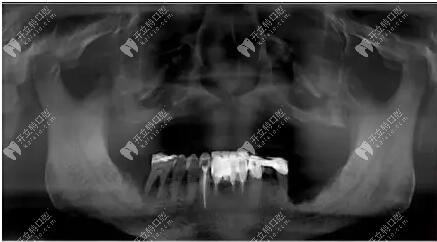

上圖看看這位大叔的具體情況

經(jīng)過(guò)拍片檢查上頜前牙區(qū)垂直骨較少,雙側(cè)上頜竇氣化明顯,患者選擇allon4和上頜結(jié)節(jié)種植,即刻修復(fù)。采用的是數(shù)字化導(dǎo)板種植,對(duì)于種植位置比較準(zhǔn)確。